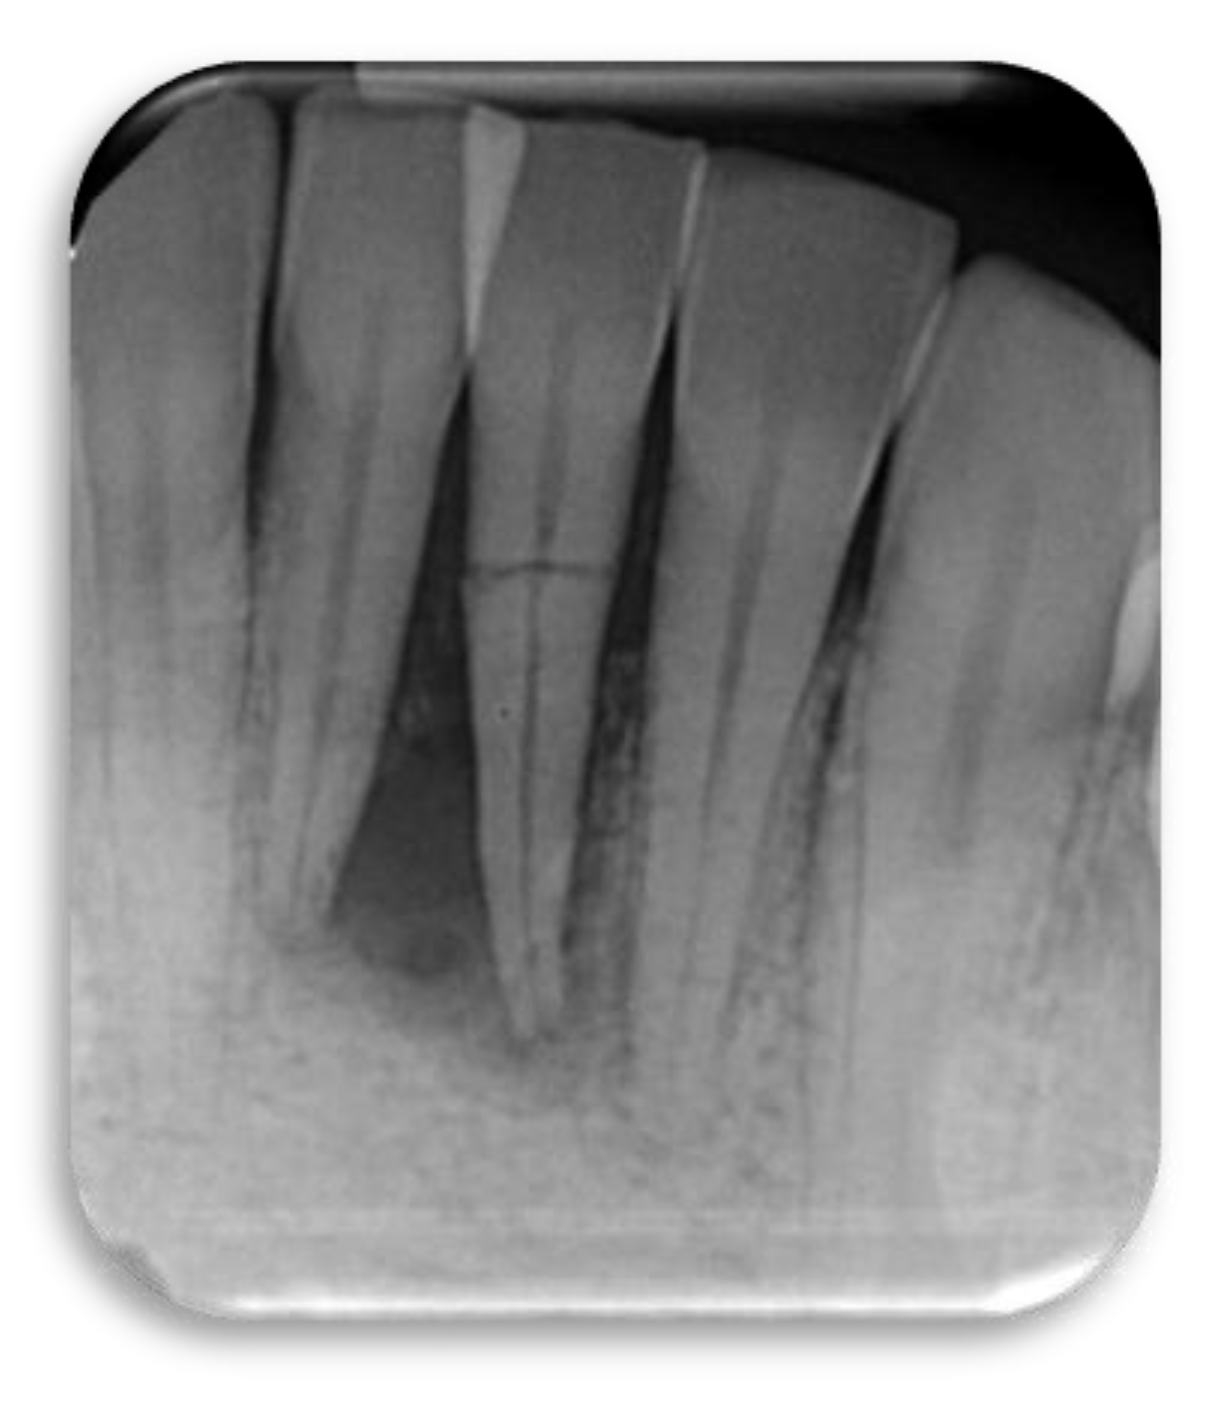

Figure 2.

Ski accident that involved a 26-year-old male. He was treated in the emergency room with a metal retainer anchored with orthodontic wire around teeth involved in the trauma (a). The diagnosis was non-complicated maxillary fracture and teeth #7, 8, and 10 concussion and #9 avulsion. Panoramic image of the metal retainer (b). After 1 month of healing, metal retainer was removed (c) and teeth #7, 8, and 10 diagnosed as necrotic. Root canal treatments were performed (d).